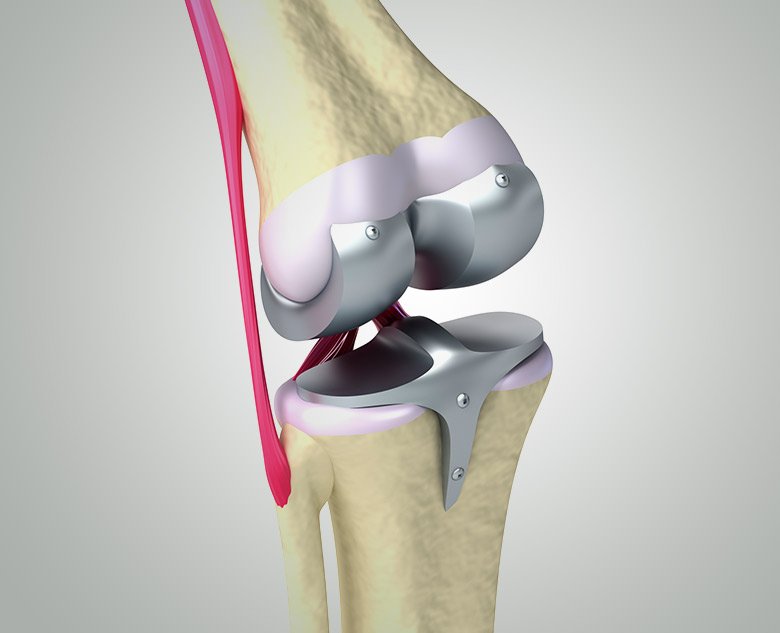

Types of Knee Replacement

We offer:

- Partial Knee Replacement – only the damaged part of the knee is replaced

- Total Knee Replacement – the entire joint is replaced

- Revision Knee Replacement – correcting or redoing a previous knee replacement